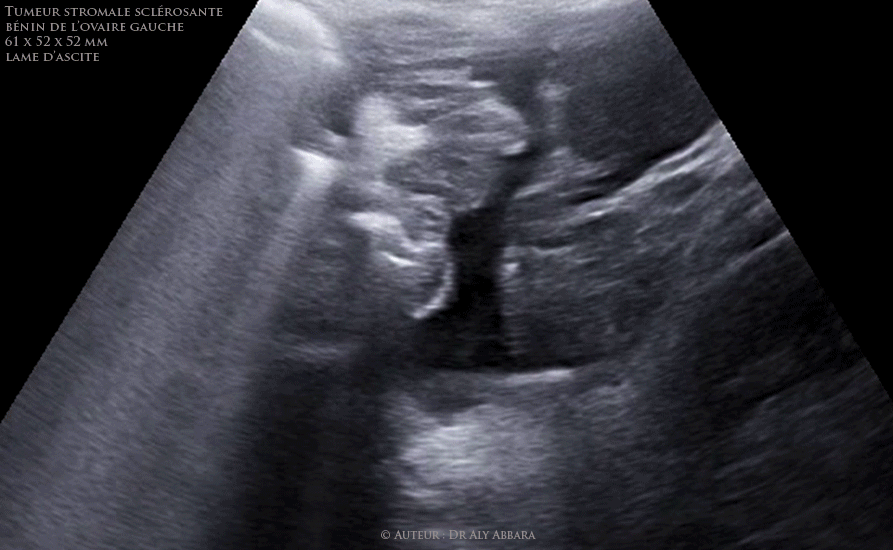

Tumeur ovarienne gauche bénigne stromale sclérosante chez une adolescente de 16 ans - images échographiques

Séquences Vidéo et images échographiques puis cliniques mettant en évidence la présence d'une tumeur ovarienne gauche, solide, bénigne, stromale sclérosante, chez une adolescente de 16 ans.

On note la présence d'une ascite de localisation pelvienne.

Cliniquement : douleurs pelviennes latéralisées à gauche depuis quelques semaines.